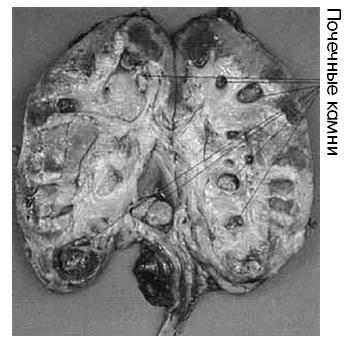

Рис. 12а. Камни внутри почек

Из-за всего этого почки перегружаются работой и больше уже не могут поддерживать нормальный баланс жидкостей в организме. Кроме того, компоненты мочи могут выпадать в осадок и формировать кристаллы и камни различных форм и размеров (см. рис. 12а). Камни из мочевой кислоты, например, формируются, когда концентрация мочевой кислоты в моче превышает 2–4 мг/дл. Это количество считалось приемлемым до середины 1960-х гг., но затем его скорректировали вверх. Мочевая кислота – побочный продукт расщепления белков в печени. Поскольку в этом десятилетии сильно повысилось потребление мяса, «норму» подправили до 7,5 мг/дл. Эта поправка, однако, не сделала мочевую кислоту сколько-нибудь менее вредной для организма. Камни, формируемые из избыточной мочевой кислоты при концентрации 4 мг/дл и более (см. также рис. 12б, «Камни в мочевом пузыре»), могут вызывать непроходимость мочевых путей, почечные инфекции и в конечном итоге почечную недостаточность.